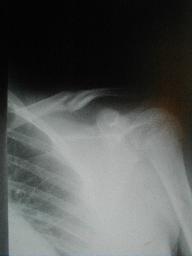

2月5日 受傷31日目

骨折部の動揺は少なくなってきた |

4月1日 受傷87日目

上腕外転位でのx-p

4月1日

運動痛 関節可動異常無し

経過良好にて治癒